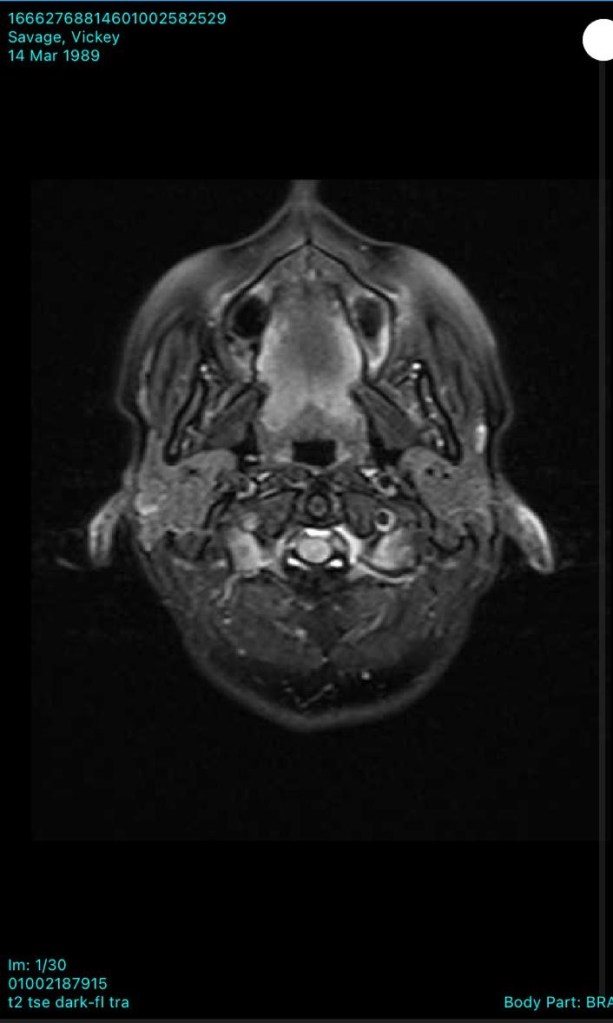

In December 2022, we later found out that there was a 13 mm cystic lesion on her pineal gland, in the limbic area of the brain, left sided. Below you will see her MRI scans from showing the cyst.

The pineal cyst in her mid brain has decreased in size, which they are also blown away by. The cyst was causing irritation to brain tissue and nerves. All physiologically induced via constant mobilisation of stressors! Through bringing down her sympathetic levels, signalling the Vagus Nerve, and inducing anti inflammatory and anti aging responses, this has been the outcome.